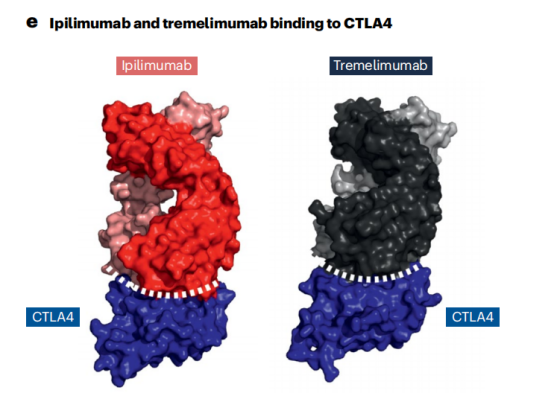

免疫检查点通过阻断抗体抑制负调节T细胞的途径,从而使细胞毒性T细胞重新活化,杀死癌细胞。已获得FDA或EMA批准的治疗性抗体靶向的三种蛋白或途径是CTLA4,PD1-PDL1和LAG3。PD1阻断抗体是目前使用最广泛的免疫检查点抑制剂。7种已获批的PD1阻断抗体和目前正在临床试验的两种使用IgG4格式,与IgG1同型相比,它不能有效激活补体级联,Fc受体结合较弱。因此,IgG4格式可能保护表达PD1的效应T细胞不被ADCC或CDC无意中杀死。所有IgG4抗体都携带S228P突变以防止Fab臂交换。通过结果生物学分析发现,PD1的2种阻断抗体pembrolizumab和nivolumab结合PD1的不同表位,并且与配体PDL1结合位点重叠,从而阻止PD1-PDL1相互作用。PDL1靶向抗体与PDL1和PDL2复合物的晶体结构鉴定了PDL2中一个关键残基(Trp100),该残基阻碍抗PDL1抗体与PDL2的结合,并提供了PDL1和PDL2之间的选择性机制。

两种CTLA4靶向抗体Ipilimumab和Tremeli-mumab具有相似的结合表位,可以有效地与天然配体CD80和CD86竞争。